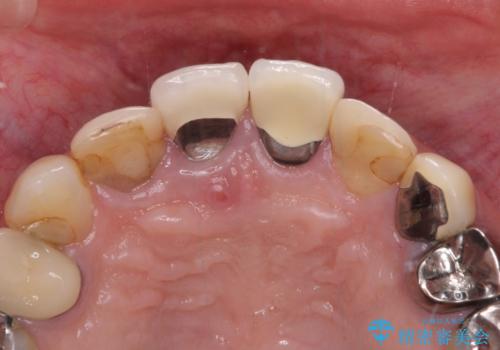

- 以前から前歯の根が折れていると言われていたものの放置しており、いよいよ痛みが気になってきたとのことで来院された患者様です。

検査の結果、右前歯の歯根が縦に破折していることが分かりました。

破折している歯は抜歯をし、歯肉が窪んでしまうので、傷口の治りを待って、歯肉移植を行うこととしました。